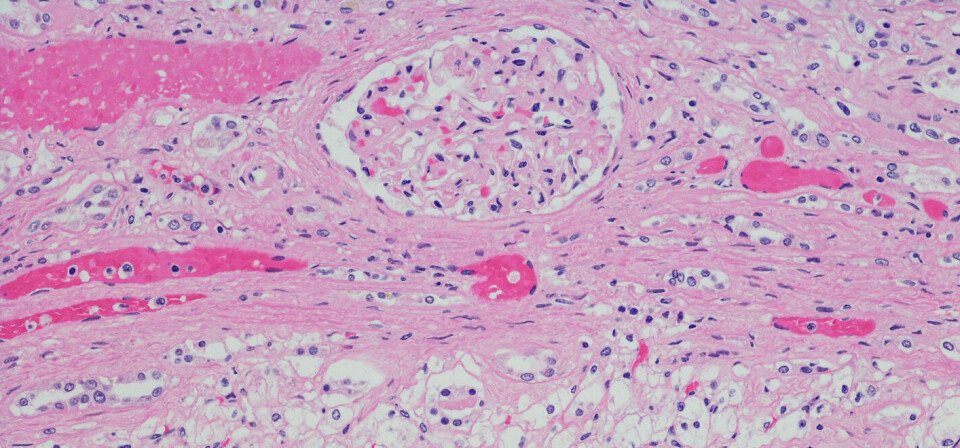

Medikamentet er allerede EU-godkjent for nyrekreft med spredning, men var også søkt EU-godkjent for å hindre tilbakefall av nyrekreft etter kirurgi. Søknaden var støttet av en placebokontrollert studie med 615 pasienter, som undersøkte hvor lang tid det tok før sykdommen kom tilbake.

Sunitinib kom først på det europeiske markedet i 2006. Foruten nyrekreft er Pfizer-medikamentet godkjent til magekreftformen gastrointestinal stromal tumor samt til pankreatisk nevroendokrin tumor.